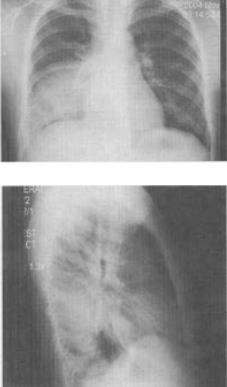

患者女,6岁半,咳嗽发热3天,体温39℃,胸片如图,最可能的诊断是()。

A、右下肺炎

B、右肺结核

C、右侧胸腔积液

D、右肺脓肿

E、右下肺不张

A